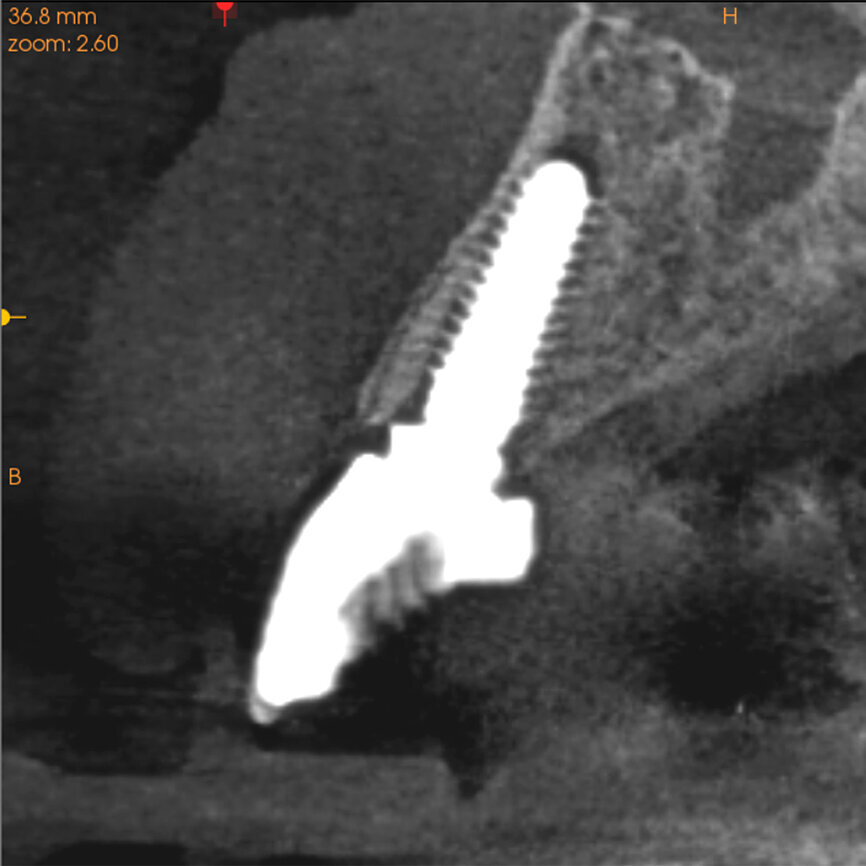

Fig. 13: The pre-op periapical radiograph revealed an existing implant-supported metal–ceramic restoration for the adjacent region #11.

Fig. 14a:

The CBCT cross-sectional image revealed a favourable pre-op condition for a PET procedure.

Fig. 14b: Using the native Carestream 3D Imaging Software,

a simulated implant (red outline) and abutment projection (yellow outline) was positioned within the available bone to avoid the root fragment.

One indication for PET is when a patient presents with a horizontally fractured clinical crown (Fig. 1). While a 2D radiograph will reveal the extent of the horizontal fracture, length of the remaining root and approximation of the bone apical to the root, there is not enough information to plan for a PET procedure. A CBCT scan is recommended in order to fully appreciate the root position within the alveolus and the potential difference between the trajectory of the bone and the trajectory of the root as can be visualised with a cross-sectional image (Fig. 2). Utilising interactive treatment planning software makes it possible to plan the initial drill path to accurately section the root to its apex (Fig. 3a). This can be accomplished by creating a custom implant design to match the diameter of the initial drill with an abutment projection in order to fully appreciate the trajectory through the clinical crown (Blue Sky Plan, Blue Sky Bio). It is important to visualise the root fragment that will remain in order to properly simulate the position of the implant in the alveolus (Fig. 3b). The apical portion of the implant can be positioned to gain stability in host bone using the Triangle of Bone. It is important to note that a cross-sectional slice may only be 0.125 mm in thickness based on the CBCT acquisition, and therefore all images in all views must be visualised to confirm the plan. Utilising 3D segmentation (separating objects by density values), it is possible to define each root and further assess the simulated position of the implant with a sagittal cut through the 3D reconstructed volume (Fig. 4).

A 62-year-old male patient presented with a hopeless prognosis for a post fracture in the left central incisor requiring extraction (Figs. 12a & b). The preoperative periapical radiograph revealed an existing implant supporting a metal–ceramic restoration for the adjacent region #11 (Fig. 13). The CBCT (CS 9600, Carestream Dental) cross-sectional image revealed a favourable preoperative condition relating to the trajectory of the endodontically treated root to the alveolus for a PET procedure (Fig. 14a). Using the native Carestream 3D Imaging software, a simulated implant and abutment projection was positioned within the available bone to avoid the root fragment (Fig. 14b).